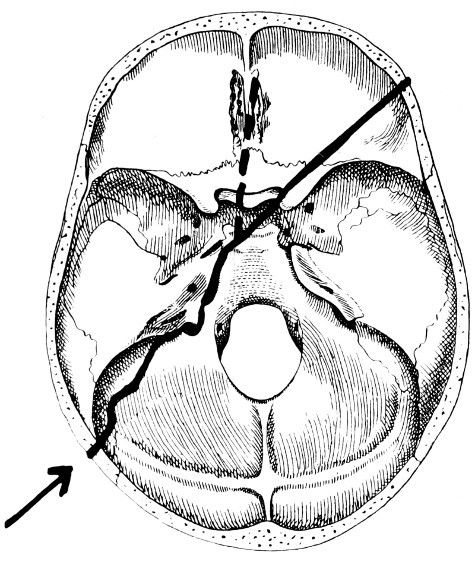

| 32-37. The lines pursued by basic fractures | 83-8 |

| 53. A basic fracture with laceration of both carotid arteries | 148 |

| 54. A basic fracture with laceration of the cavernous sinus | 149 |

| 55. A basic fracture with laceration of both lateral sinuses | 151 |